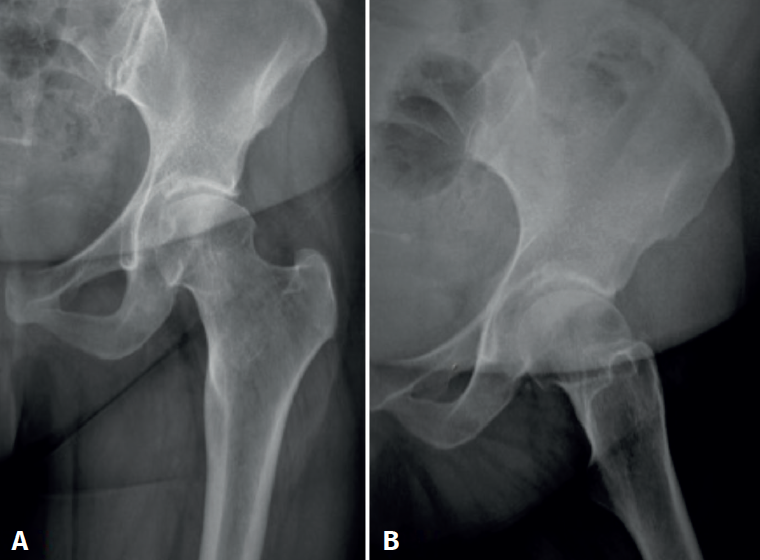

The postoperative radiographs (Figure 6) showed complete resection of the tumour, with correct joint congruence. The pathology findings were consistent with osteochondroma (Figure 7). The clinical course was favourable during the first year, with weight bearing using crutches for 6 weeks, followed by physiotherapy. The symptoms subsequently reappeared, with mechanical pain in the inguinal region that increased in intensity with rotation and caused limitation of her daily activities - the Harris Hip Score being 34 points out of 100. A new magnetic resonance imaging study revealed femoroacetabular impingement and thinning of the joint cartilage (Figure 8). A total hip arthroplasty was therefore proposed and carried out 18 months after arthroscopic resection of the osteochondroma. The femoral head was sent for histopathological study, which confirmed the existence of residual osteochondroma (Figure 9).